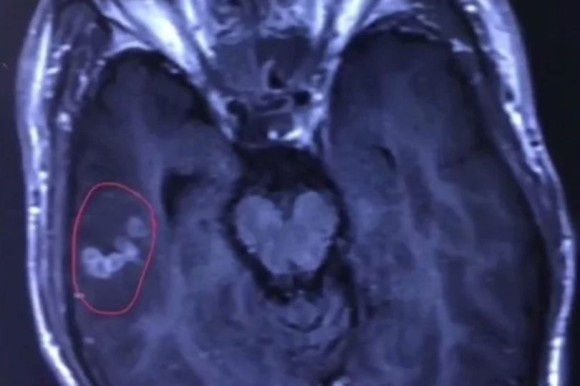

男性の脳内に潜んでいた条虫

血液検査から、なんとリュウの脳内にはマンソン裂頭条虫がいることがわかった。

南昌大学病院で手術が行われたが、担当医によると、取り出された条虫はまだ生きていて、全身が白くて元気がよく、泳ぎ回ることができたという。

男性の脳にいた条虫は体長10センチもあり生きていた